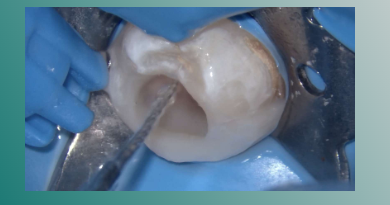

机械化学预备后

吸潮纸尖干燥根管

根管内注入氢氧化钙糊剂

髓腔内放置一无菌小棉球,蓝色玻璃离子暂封。

一周复诊,疼痛消失,叩 (-),替封完好。